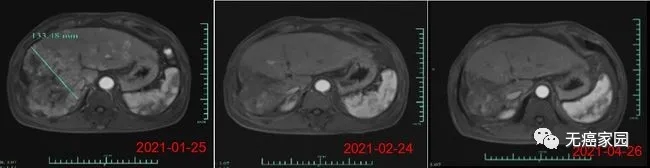

在数据截止时,受试者007的部分缓解时间6个月,其肿瘤体积在细胞治疗输注后1个月减少了80%以上。(截至2021年6月,该受试者已超过8个月的疾病控制,随访仍在进行中)。受试者012是1例弥漫型、巨块型晚期肝癌患者,曾接受过12次以上的TACE治疗、放疗及靶向治疗,不幸的是均无效,随后参与本研究。

在输注CAR-T细胞后的第28天,受试者MRI结果显示最大肿瘤直径从最初的133毫米减少至9毫米,缩小超过93%。目前,该受试者正在接受CAR-T细胞输注后第3个月的评估,MRI扫描显示此肿瘤几乎消失。此外,甲胎蛋白(AFP,原发性肝癌的特定肿瘤标志物)水平从基线值 >80,000/ng/ml 下降到第1个月的1148.9ng/ml,并在第3个月下降到746.7ng/ml输注(正常范围<40ng/ml),证明 Ori-CAR-001 在晚期肝癌患者中具有显著的初步疗效。

受试者012的MRI结果示意图